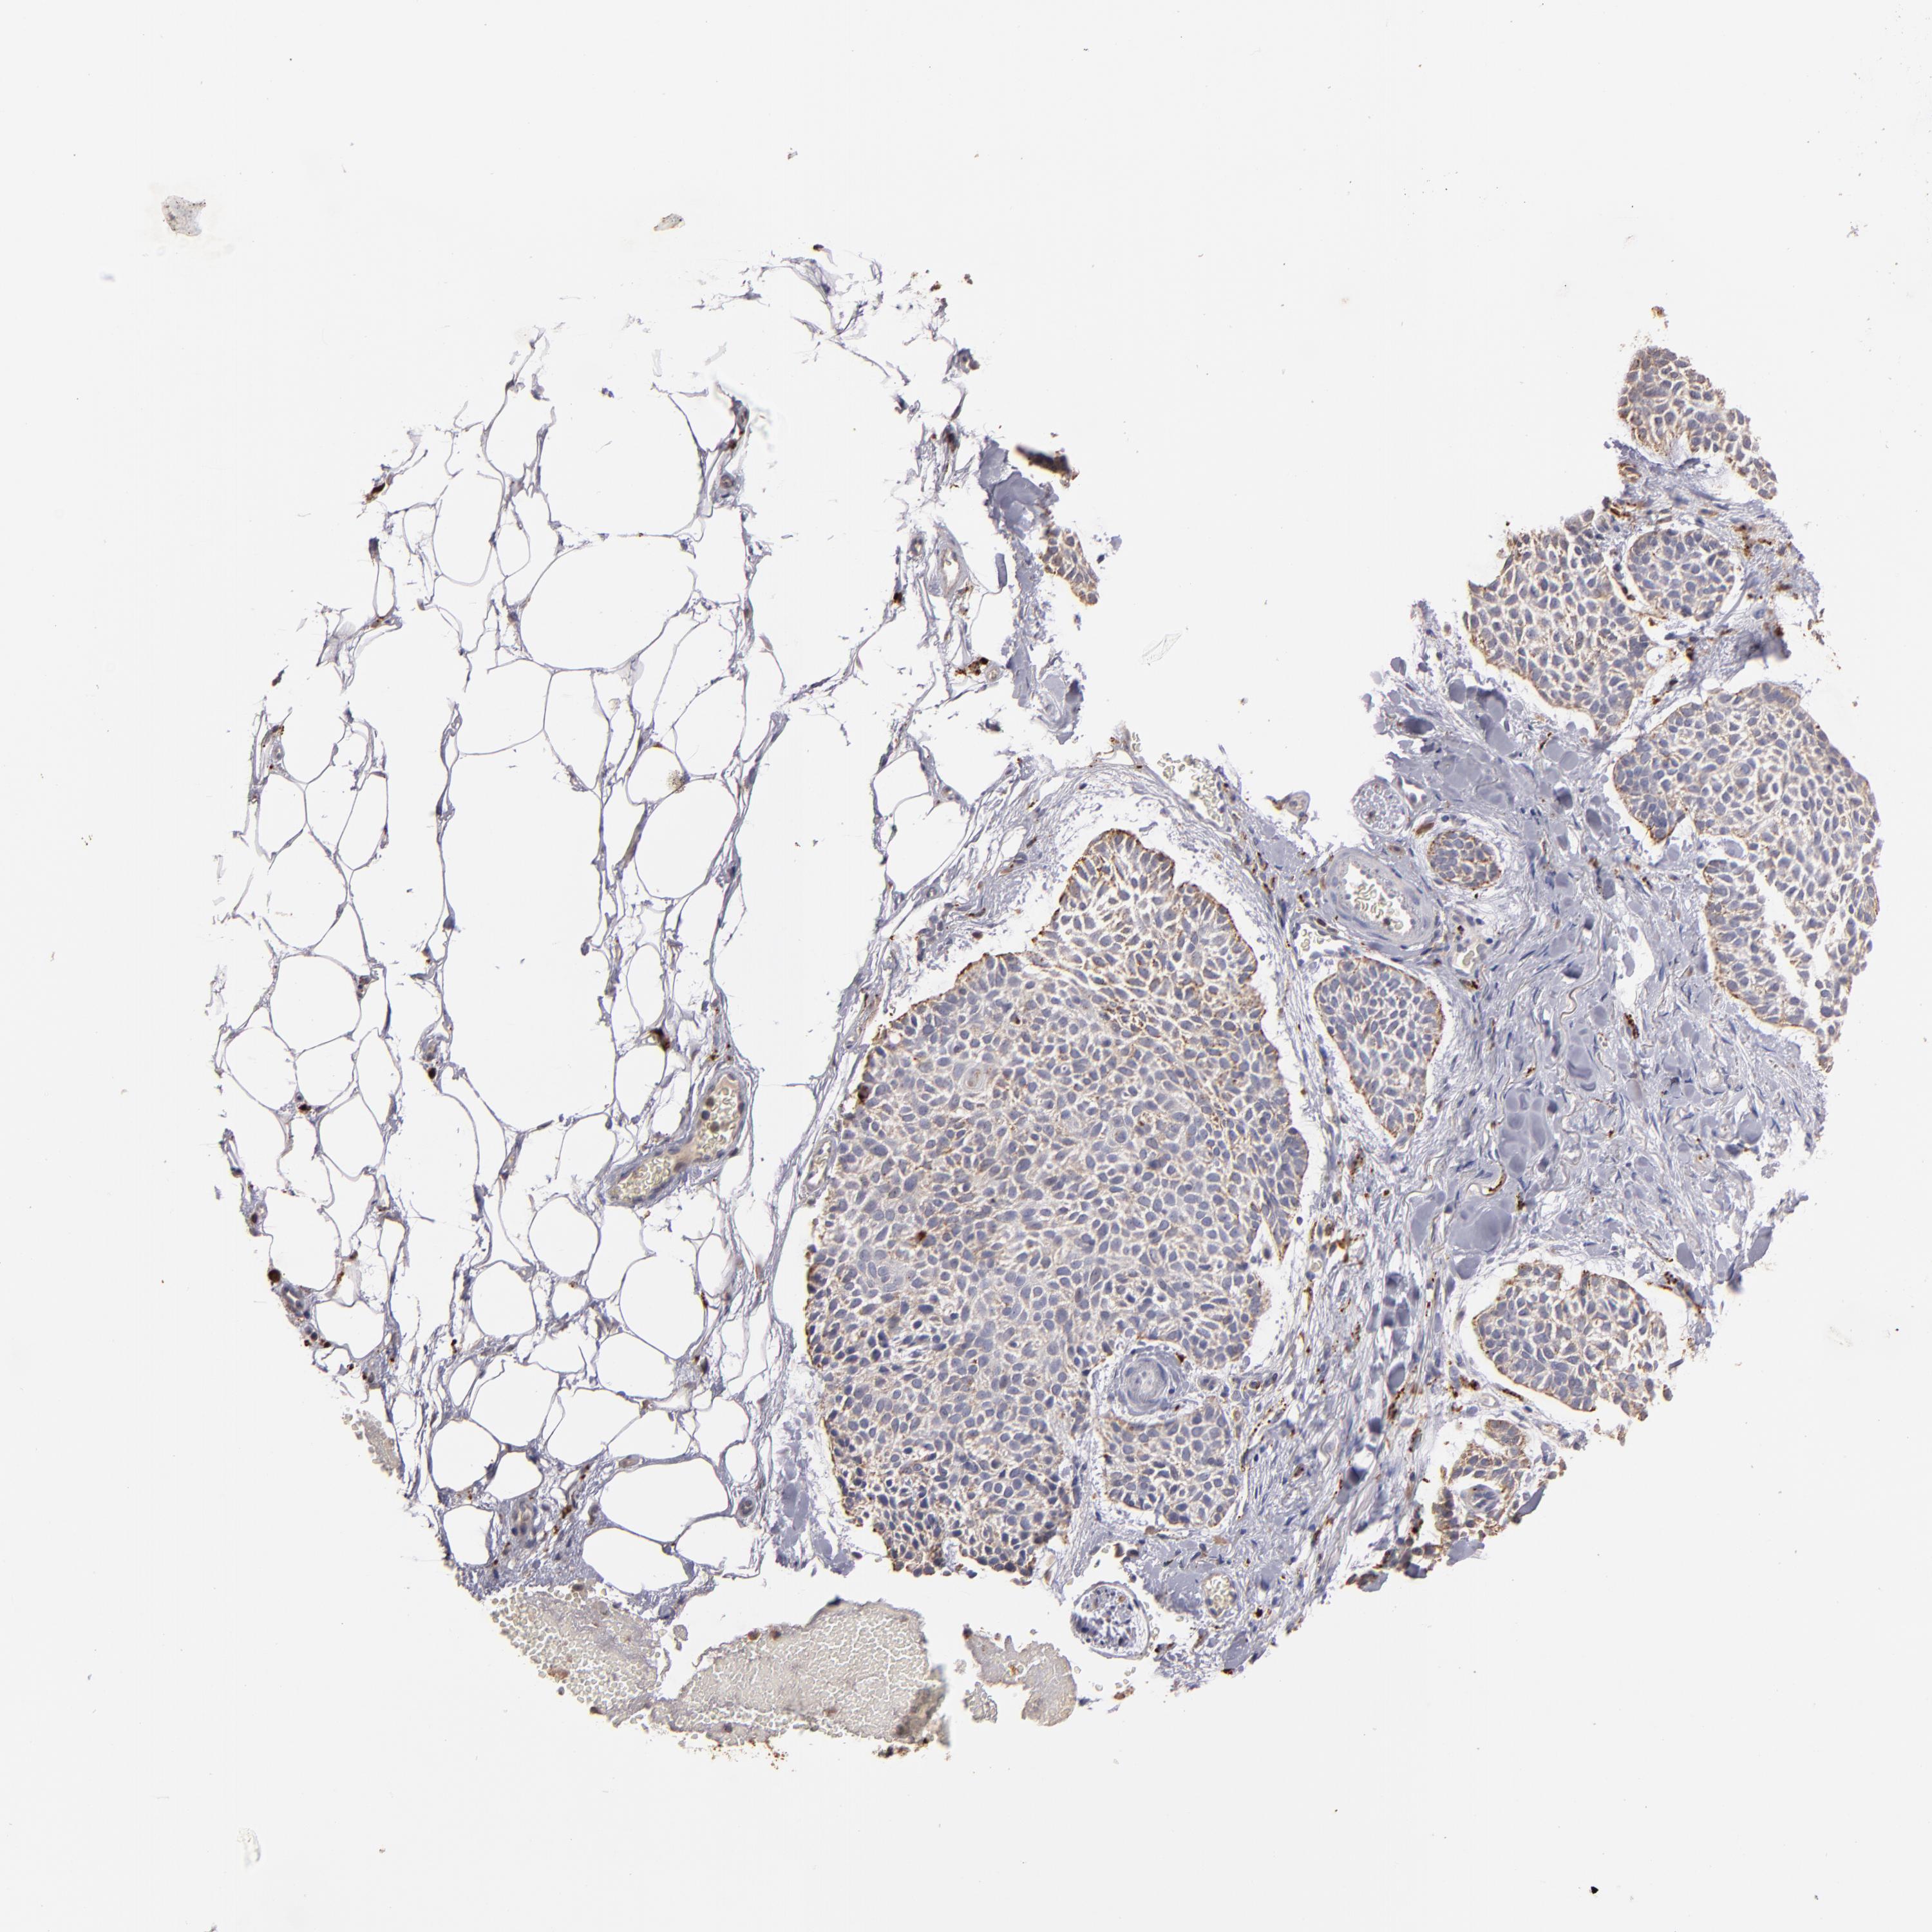

SKIN CANCER - Protein expressioni

A mouse-over function shows sample information and annotation data. Click on an image to view it in a full screen mode. Samples can be filtered based on level of antibody staining by selecting one or several of the following categories: high, medium, low and not detected. The assay and annotation is described here.

Each image is clickable and will lead to virtual microscopy that enables deeper exploration of all samples and also displays staining intensity scores, fraction scores and subcellular localization as well as patient and tissue information for each sample.

Antibody HPA001852

Squamous cell carcinoma, NOS

Basal cell carcinoma